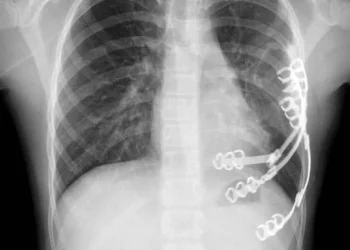

ויולטה הגיעה לישראל במסגרת תיירות מרפא, לאחר שהגידול בגופה הפך בלתי ניתן לשליטה. במשך חודשים עברה תשעה סבבים של כימותרפיה, עד שניתן היה לגשת לניתוח. הסרת הגידול כולו יחד עם חלק מכלוב הצלעות שנפגע, והשתלת שתלים מיוחדים עשויי טיטניום במקומו.

מדובר בניתוח ראשון מסוגו בבית החולים, שנוהל בשיתוף פעולה בין צוותים מבתי החולים שניידר ובילינסון, בהובלת דוקטור יורי פייסחוביץ מבילינסון ודוקטור מיכאל סגל משניידר.